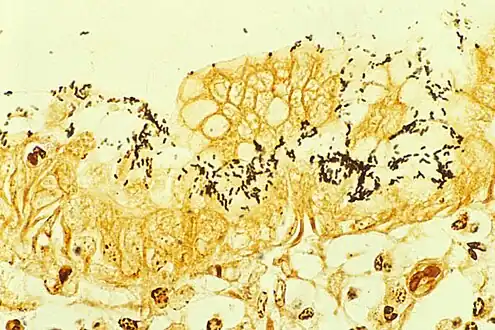

![]() | |

| Immunohistochemical staining of H. pylori (brown) from a gastric biopsy | |

H. pylori colonized on the surface of regenerative epithelium (Warthin-Starry silver stain)